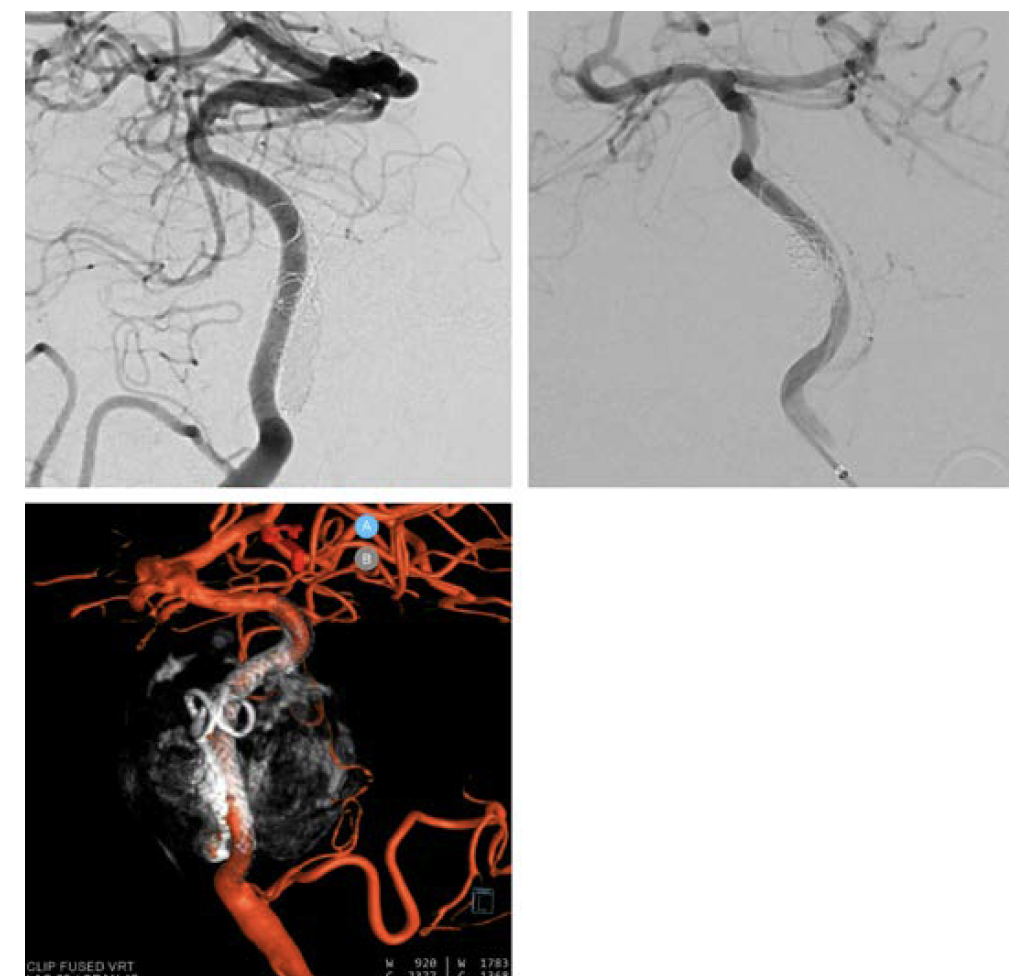

In the first case, a healthy 59-year-old patient presented to the ER with aneurysmal subarachnoid hemorrhage and an unusual ruptured right internal carotid artery dorsal wall aneurysm (Figure 6). While each practice approaches these somewhat differently, this is a flow diversion case for Goodman Campbell Brain and Spine.

Access in a case such as this must be obtained with extreme care and the utmost precision. Note the clarity and visualization of the support catheter (0.058" Navien [Medtronic]) and microcatheter (Phenom 27 [Medtronic]), even without the presence of a wire (Figure 7).

A 3D reconstruction of the aneurysm and DynaCT Micro image of the stent construct was performed (Figure 8). This is a 3-stent construct. There was extraordinary coverage over the neck of the aneurysm with 2-stent coverage over the distal ophthalmic segment and 1-stent coverage extending into the cavernous segment.

The patient returned for a 6-month follow-up angiography (Figure 9). 3D DSA and DynaCT Micro fusion imaging demonstrated the stent construct and aneurysm segment. The aneurysm was cured, and the patient was neurologically normal and returned to work.